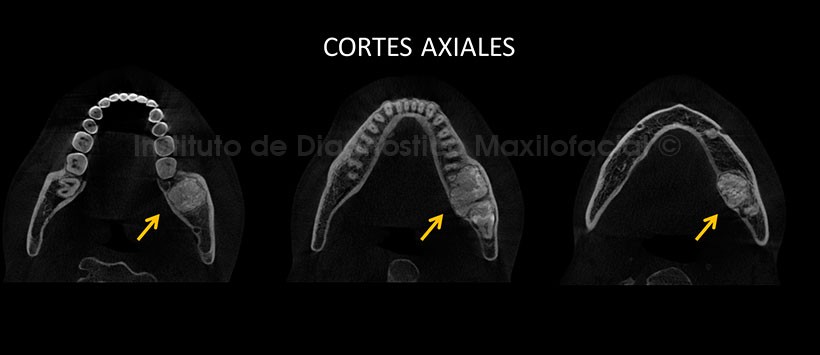

En los cortes axiales de maxilar inferior, pudimos observar el aumento de tamaño de la tabla ósea lingual y vestibular, siendo esta ultima la de mayor predominio (Figura 2). Así mismo en los cortes transaxiales y tangenciales podemos observar la estrecha relación de esta lesión con los ápices de la pieza 37, también se aprecia el adelgazamiento de a cortical lingual a causa de esta lesión y el desplazamiento hacia caudal del conducto dentario inferior. (Figura 3 y Figura 4)